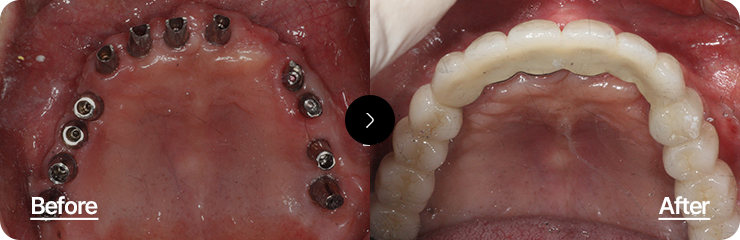

상실된 치아 전체를 복원하여

자연스럽고 건강한 구강 기능 회복

최소한의 임플란트로 최적의 위치에 식립하여 기능과 심미성을 동시에 회복하는 치료입니다.

정확한 교합 분석과 풍부한 임상 경험이 요구되는 고난이도 시술입니다.